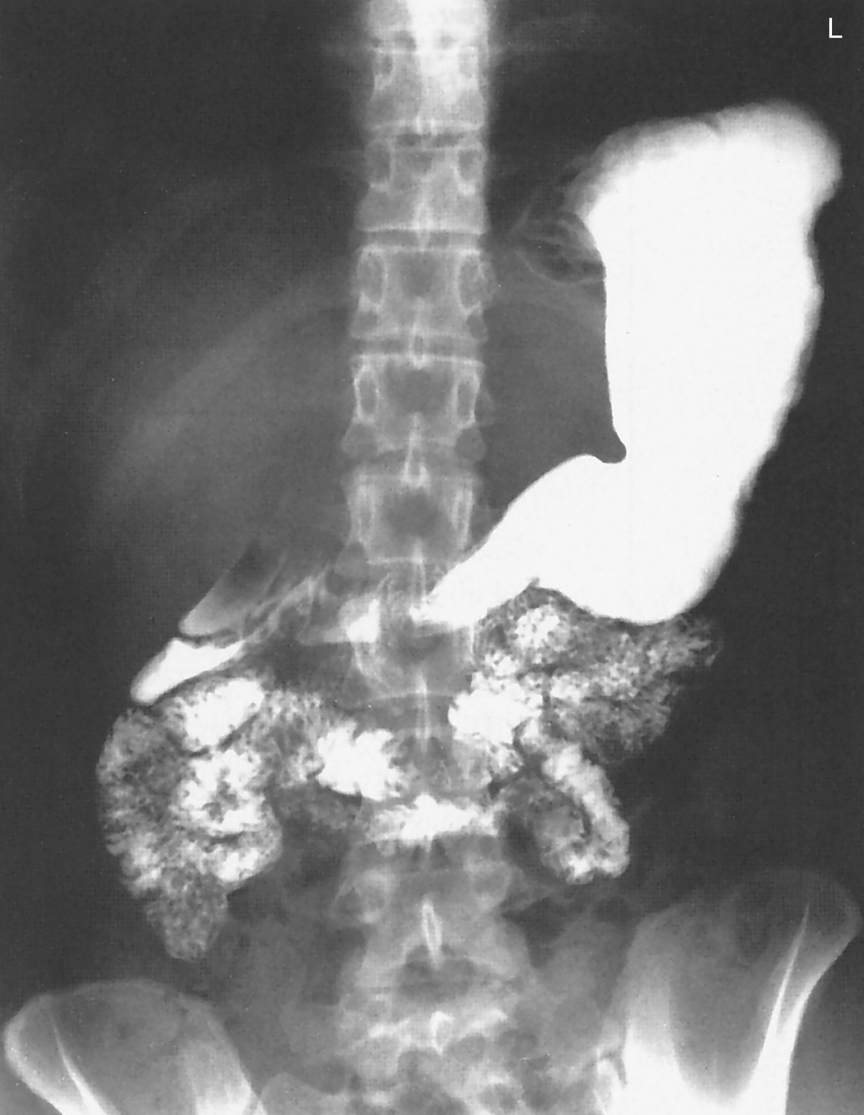

Upper gastrointestinal study with small bowel follow-through revealing ...